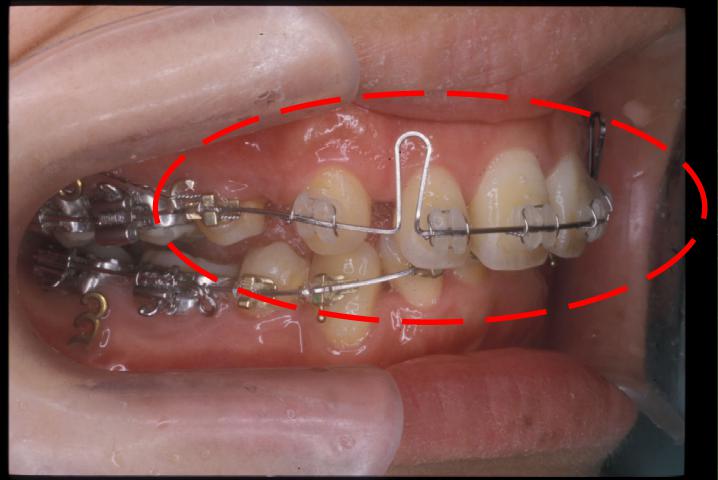

Loop đóng khoảng răng cửa là một khí cụ chỉnh nha được thiết kế đặc biệt để di chuyển các răng cửa lại gần nhau, từ đó đóng kín các khoảng trống giữa chúng. Khí cụ này thường được làm từ dây cung chỉnh nha có hình dạng đặc trưng với các vòng (loop) được uốn cong một cách tỉ mỉ. Các loop này có vai trò tạo lực kéo liên tục và nhẹ nhàng lên các răng, giúp chúng di chuyển một cách ổn định và hiệu quả.